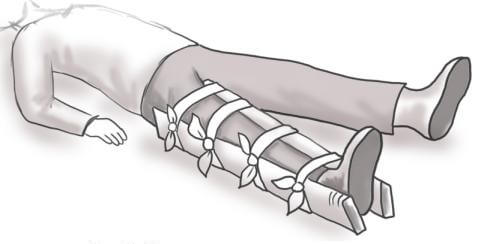

Мультяшные сломанные кости: Рисунки и комиксы

Раздел: Фотоархив